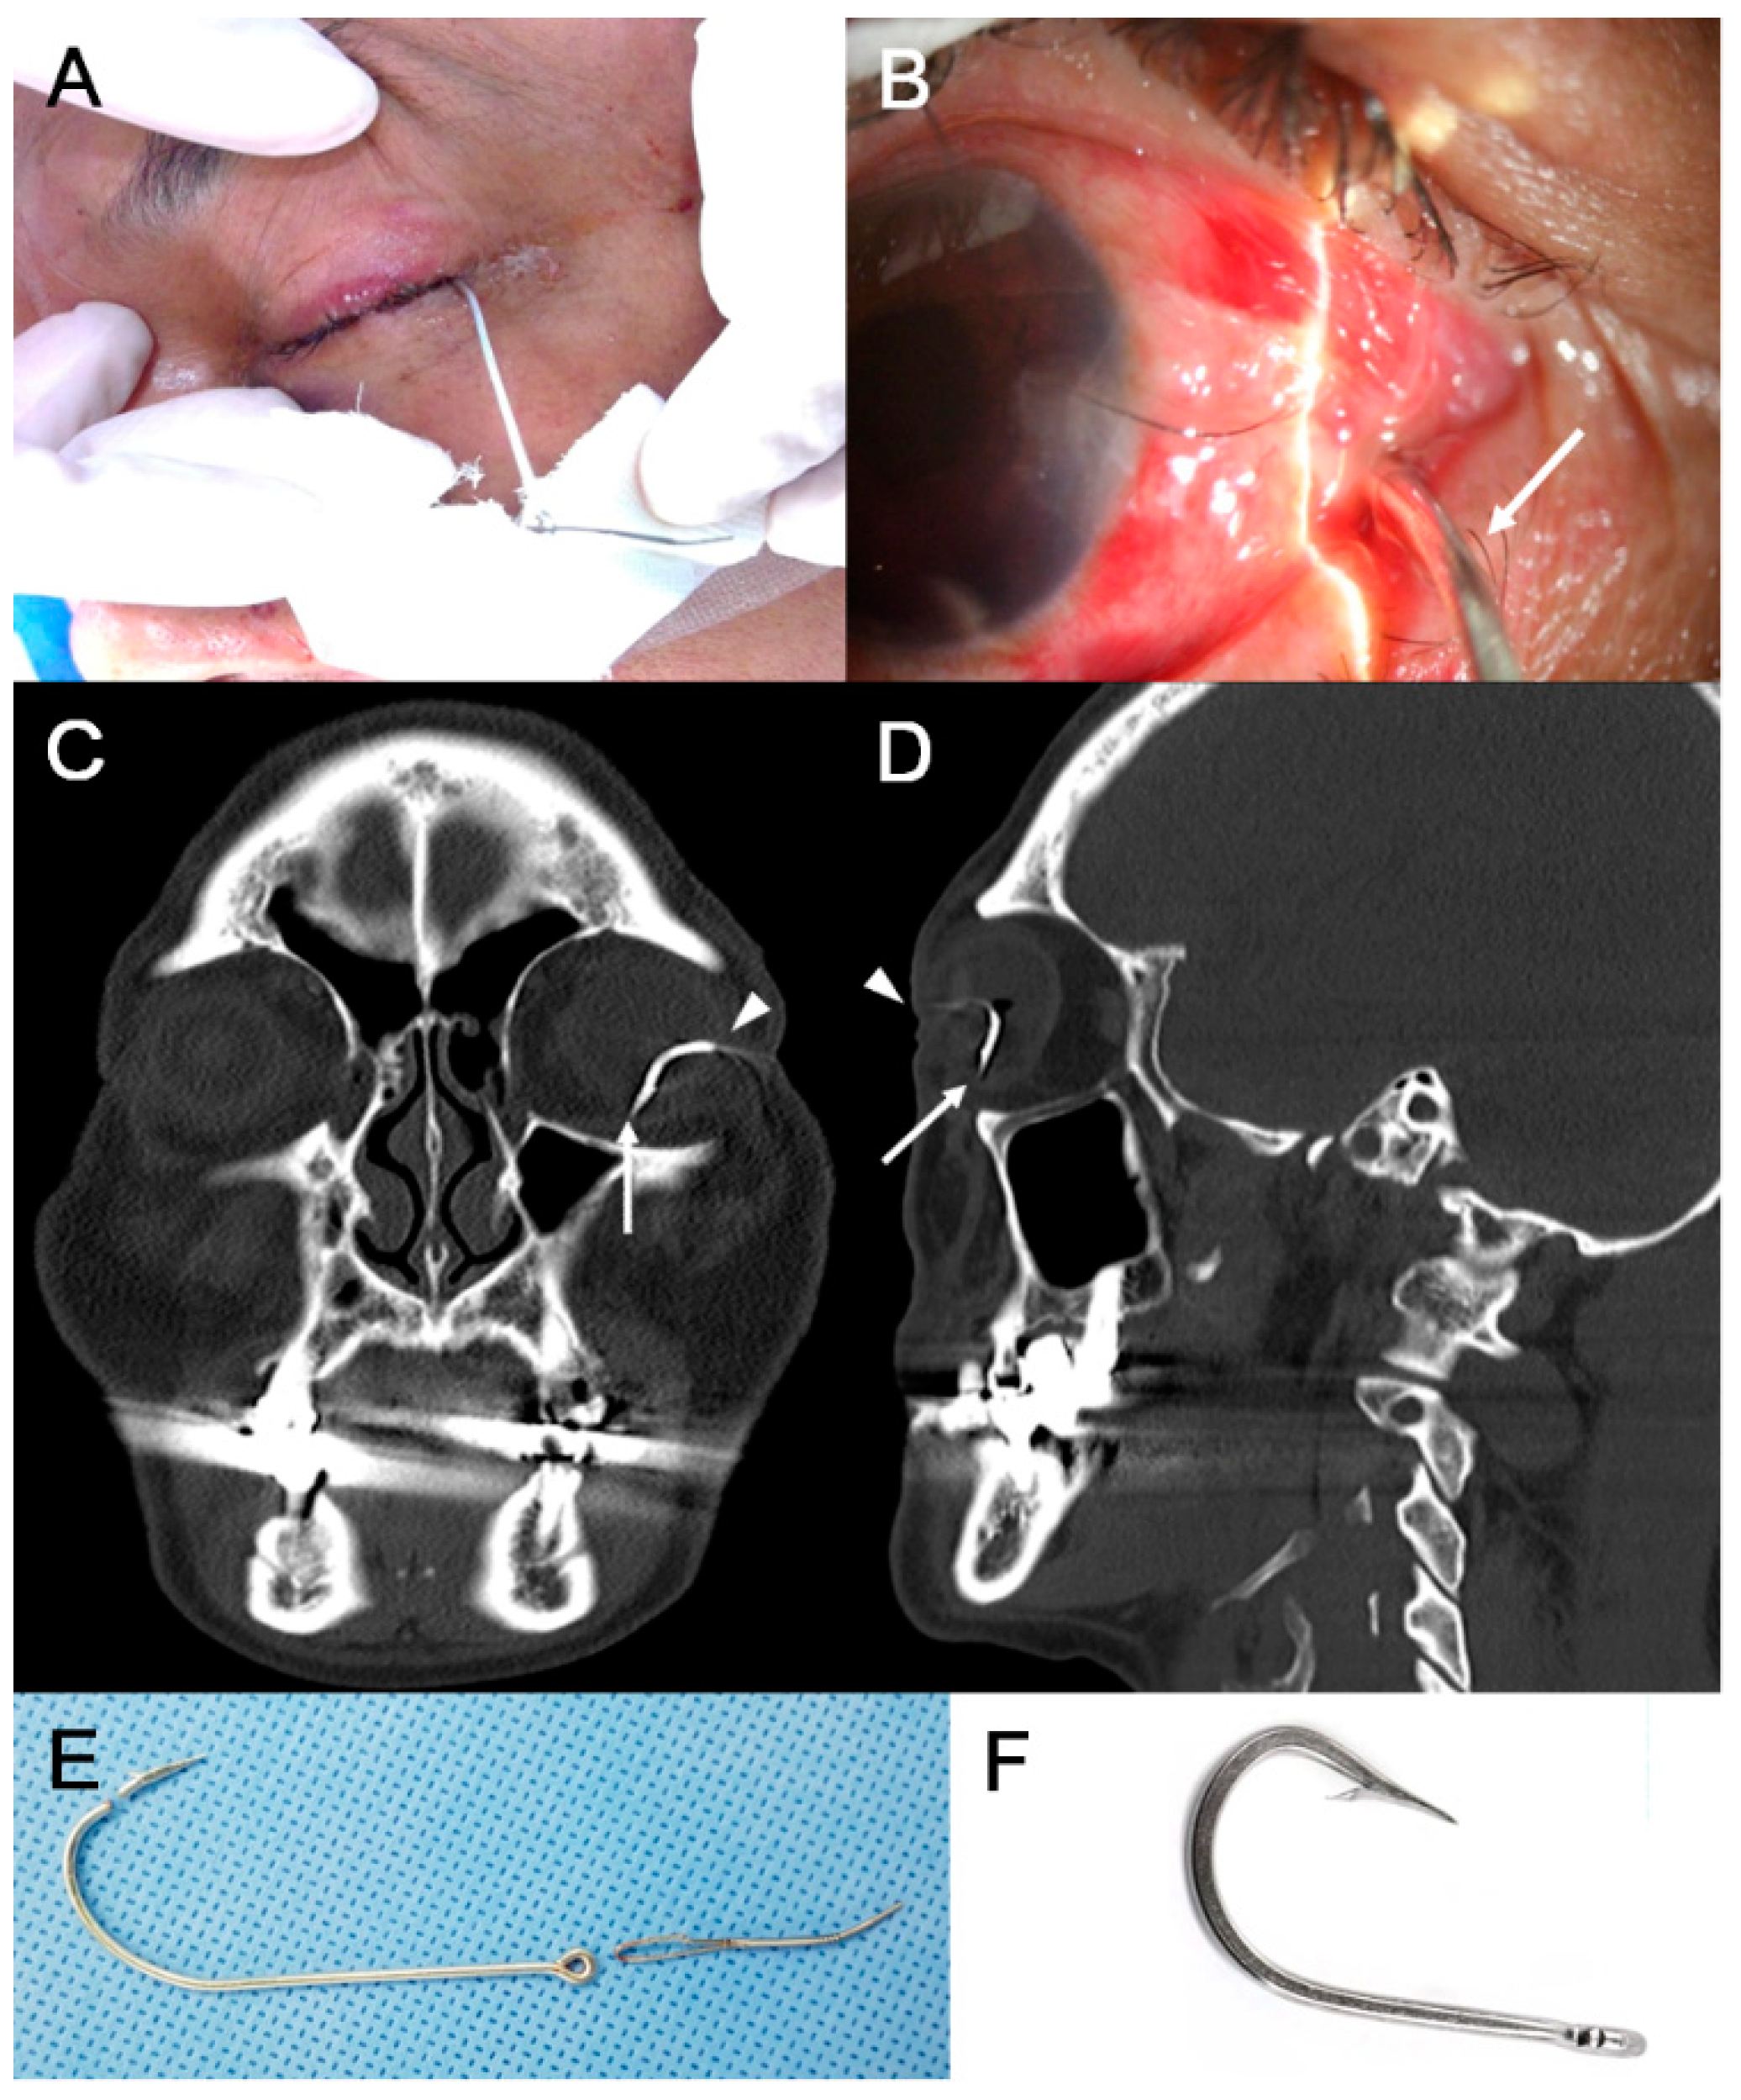

| Fishhook | 2 (3.8%) |